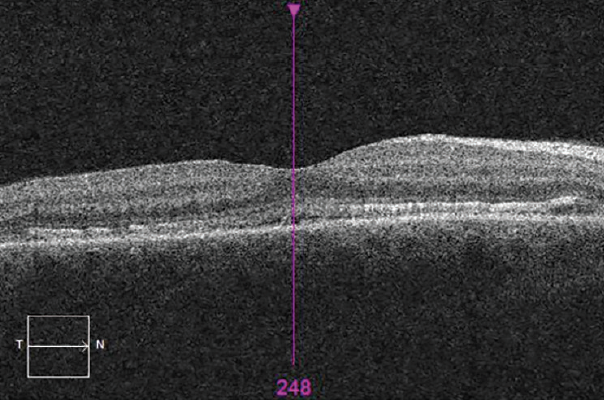

Spectral-domain OCT showed irregularity and thickening of the retinal pigment epithelium (RPE) layer, hyper-reflectivity of the outer nuclear layer, and obliteration of the outer limiting membrane in the macular region of each eye. The macula OD also showed evidence of subretinal fluid (SRF) at the fovea (Figures 4 and 5).

<p>Figure 4. OCT showing irregularity and thickening of the RPE and obliteration of the outer limiting membrane in the macular region OD. The macula showed evidence of subfoveal fluid.</p>

Figure 4. OCT showing irregularity and thickening of the RPE and obliteration of the outer limiting membrane in the macular region OD. The macula showed evidence of subfoveal fluid.